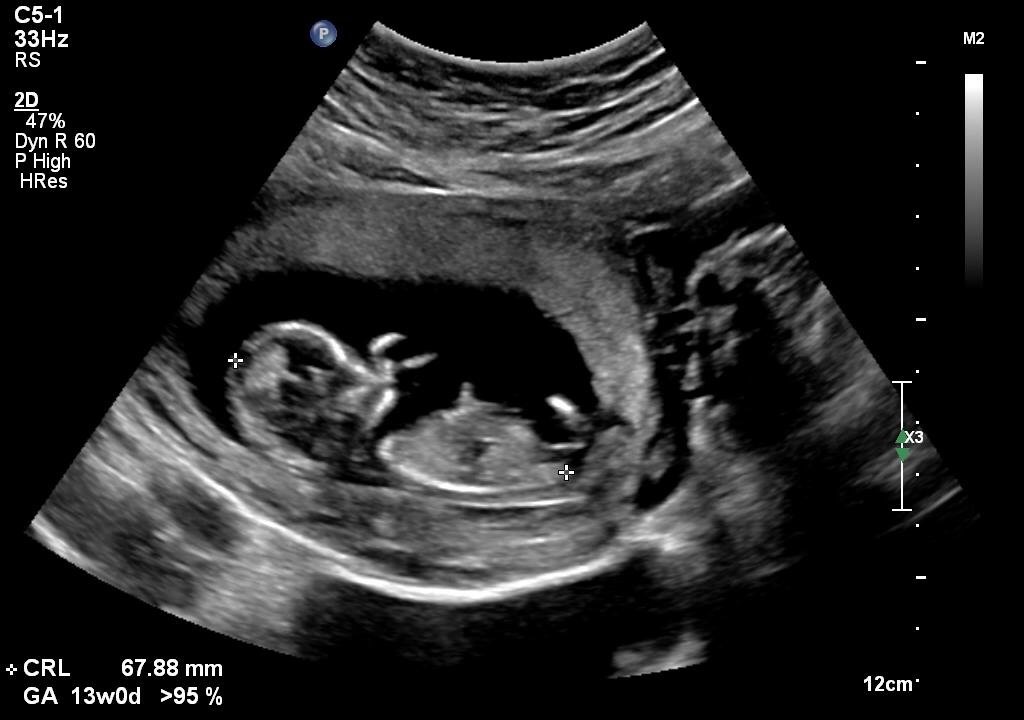

Nub gender guess! 12+3

Hi would love some gender guesses!

We swayed boy but not holding out a lot of hope. Tech said she could maybe see something between the legs but wasn't sure!

Will update from gender scan in 2 weeks! Attachment 30321

I am def not an expert but the top one looks girly while the bottom one looks like a boy! Sorry - probably the least helpful reply ever... I hope you hear boy x

I think girl based on the top picture; the other pics look like baby has turned onto its side...x

First pic looks like girly. But last one is a bit angled.